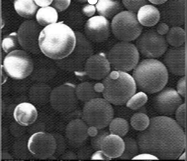

2000倍显微镜图

水凝胶球体结构稳定,有效降低滑动摩擦力,润滑作用显著;

凝胶骨架结构图

黏附性好,易于涂布成膜,有效形成粘膜表面缓冲层